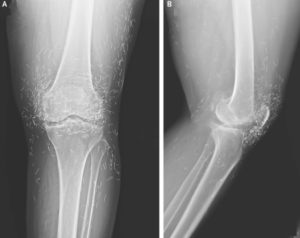

Acupuncture, a centuries‑old alternative treatment, involves inserting needles into specific points on the body to relieve pain or treat illness. In this instance, the needles — presumably made of gold — were intentionally left in her knees for continued stimulation.

He also warned that embedded needles can complicate X‑ray readings. “The needles may obscure some of the anatomy,” Guermazi said in 2013.

“The human body wants to get rid of the foreign object,” Guermazi explained. “It starts with some mechanism of defense, for example inflammation and forming [fibrous tissue] around the object.” Even more concerning, needles left in the body can make future medical imaging dangerous. “The patient can’t go into an MRI because needles left in the body may move and damage an artery,” Guermazi added.